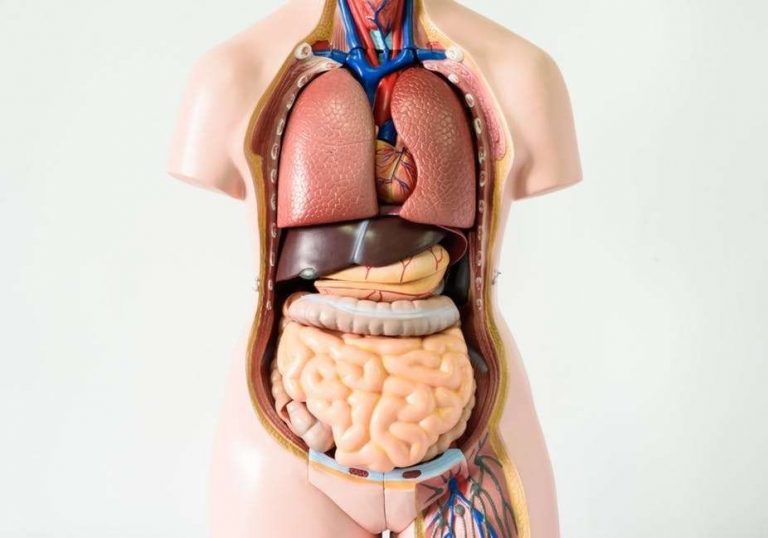

العضو عبارة عن مجموعة من الأنسجة المختلفة التي تعمل معًا للقيام بعمل معين. يتم تجميع الأعضاء معًا في أنظمة الأعضاء. من أمثلة أجهزة الجسم الجهاز الدوري والجهاز الهضمي.

ما هي أعضاء جسم الإنسان

أنواع الأعضاء

يتم تجميع أعضاء جسم الإنسان في أنظمة الأعضاء بناء على الوظائف التي يؤدونها. البشر لديهم 11 أجهزة مختلفة. فيما يلي أمثلة الأعضاء الموجودة في كل نظام:

- الغلاف (الجلد والشعر والأظافر).

- الهيكل العظمي (العظام).

- العضلات (العضلات الملساء والقلبية والهيكل العظمي).

- الدورة الدموية (القلب والشرايين والأوردة).

- الجهاز التنفسي (الرئتين، الحجاب الحاجز، الحنجرة).

- الجهاز الهضمي (المعدة والأمعاء والكبد).

- المسالك البولية (الكلى والحالب والمثانة).

- المناعة (الغدد الليمفاوية، نخاع العظام، الغدة الصعترية).

- عصبي (الدماغ والحبل الشوكي والأعصاب).

- الغدد الصماء (الغدة النخامية، الغدة الدرقية، الغدة الكظرية).

- التناسلية (القضيب، المهبل، البروستاتا، الرحم).

وظائف أعضاء الجسم

أعضاء جسم الإنسان توجد داخل أنسجة مختلفة تعمل معًا لتنفيذ وظيفة معينة. هذه هي الأجهزة الرئيسية، وكذلك وظيفتها الأساسية: